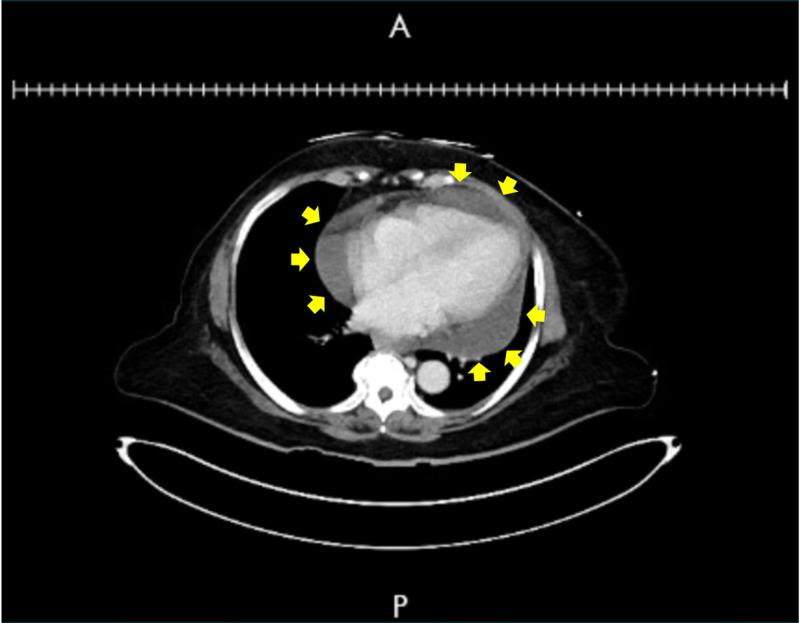

肼屈嗪诱发的狼疮综合征(HILS)是一种临床表现多样的罕见临床病症。心包受累是该病症一种不常见但严重的表现。在本报告中,我们呈现了一例继发于HILS的大量有症状心包积液病例。我们强调了对这一罕见综合征进行评估和管理时的重要注意事项。对于服用每日100毫克或更多肼屈嗪超过三个月、病因不明的心源性心包填塞患者,鉴别诊断时应考虑HILS。致病药物与出现症状之间的时间关联、停药后症状缓解以及抗组蛋白抗体检测呈阳性均有助于支持该综合征的诊断。